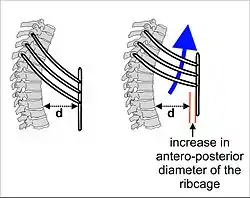

The lungs are not capable of inflating themselves, and will expand only when there is an increase in the volume of the thoracic cavity.[6][7] In humans, as in the other mammals, this is achieved primarily through the contraction of the diaphragm, but also by the contraction of the intercostal muscles which pull the rib cage upwards and outwards as shown in the diagrams on the right.[8] During forceful inhalation (Figure on the right) the accessory muscles of inhalation, which connect the ribs and sternum to the cervical vertebrae and base of the skull, in many cases through an intermediary attachment to the clavicles, exaggerate the pump handle and bucket handle movements (see illustrations on the left), bringing about a greater change in the volume of the chest cavity.[8] During exhalation (breathing out), at rest, all the muscles of inhalation relax, returning the chest and abdomen to a position called the "resting position", which is determined by their anatomical elasticity.[8] At this point the lungs contain the functional residual capacity of air, which, in the adult human, has a volume of about 2.5–3.0 liters.[8]